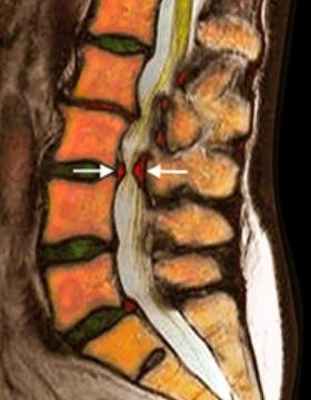

![стеноз в пояснице в цвете]()

МРТ поясничного отдела позвоночника. Т2-взвешенная сагиттальная МРТ. Стеноз позвоночного канала.